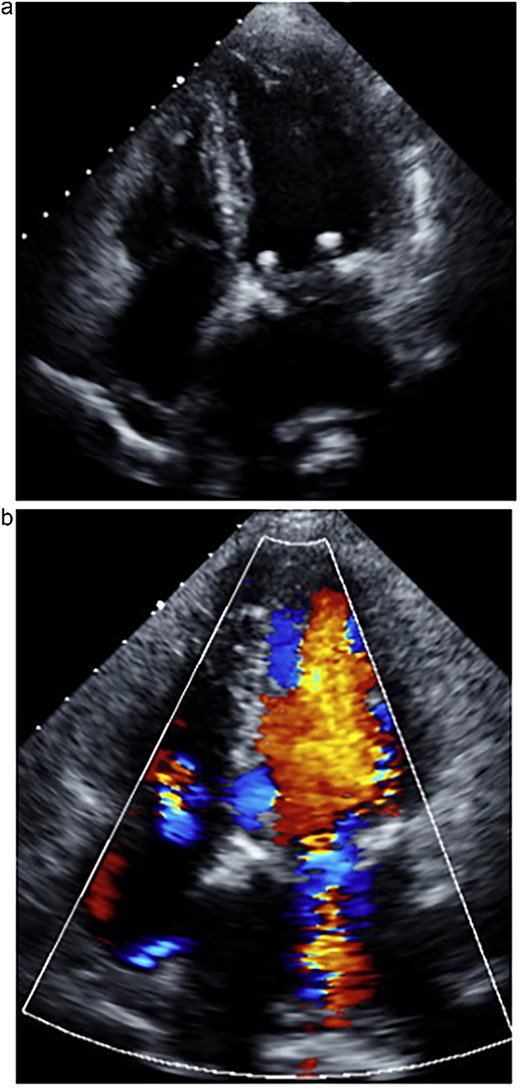

Transesophageal echocardiography following the MitraClip procedure. (a) The posterior mitral leaflet is torn, resulting in a loss of continuity. (b) Mitral regurgitation is observed originating from the site of the tear.

An 80-year-old woman with a history of chronic kidney disease, ulcerative colitis, and dyslipidemia had been followed for severe MR for the past 6 years. She presented with progressive dyspnea and was admitted with acute decompensated heart failure. Transthoracic echocardiography (TTE) demonstrated significant prolapse of the A3 segment and a markedly reduced left ventricular ejection fraction (LVEF) of 30%. Given her frailty, impaired ventricular function, and multiple comorbidities, conventional surgical mitral valve repair was deemed high risk. Therefore, the MitraClip system was selected and performed by the cardiology team. During the MitraClip procedure, however, a posterior mitral leaflet tear occurred, resulting in worsened severe MR (Fig. 1). Consequently, the patient was referred to our department for operation.